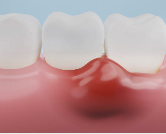

✅ 7. 잇몸이 약간 내려앉은 느낌

잇몸이 조금씩 내려가면 치아 뿌리가 노출되기 시작하고,

치은염이 심화되면 치주염으로 이어져 치아가 흔들리거나 빠질 수 있어요.